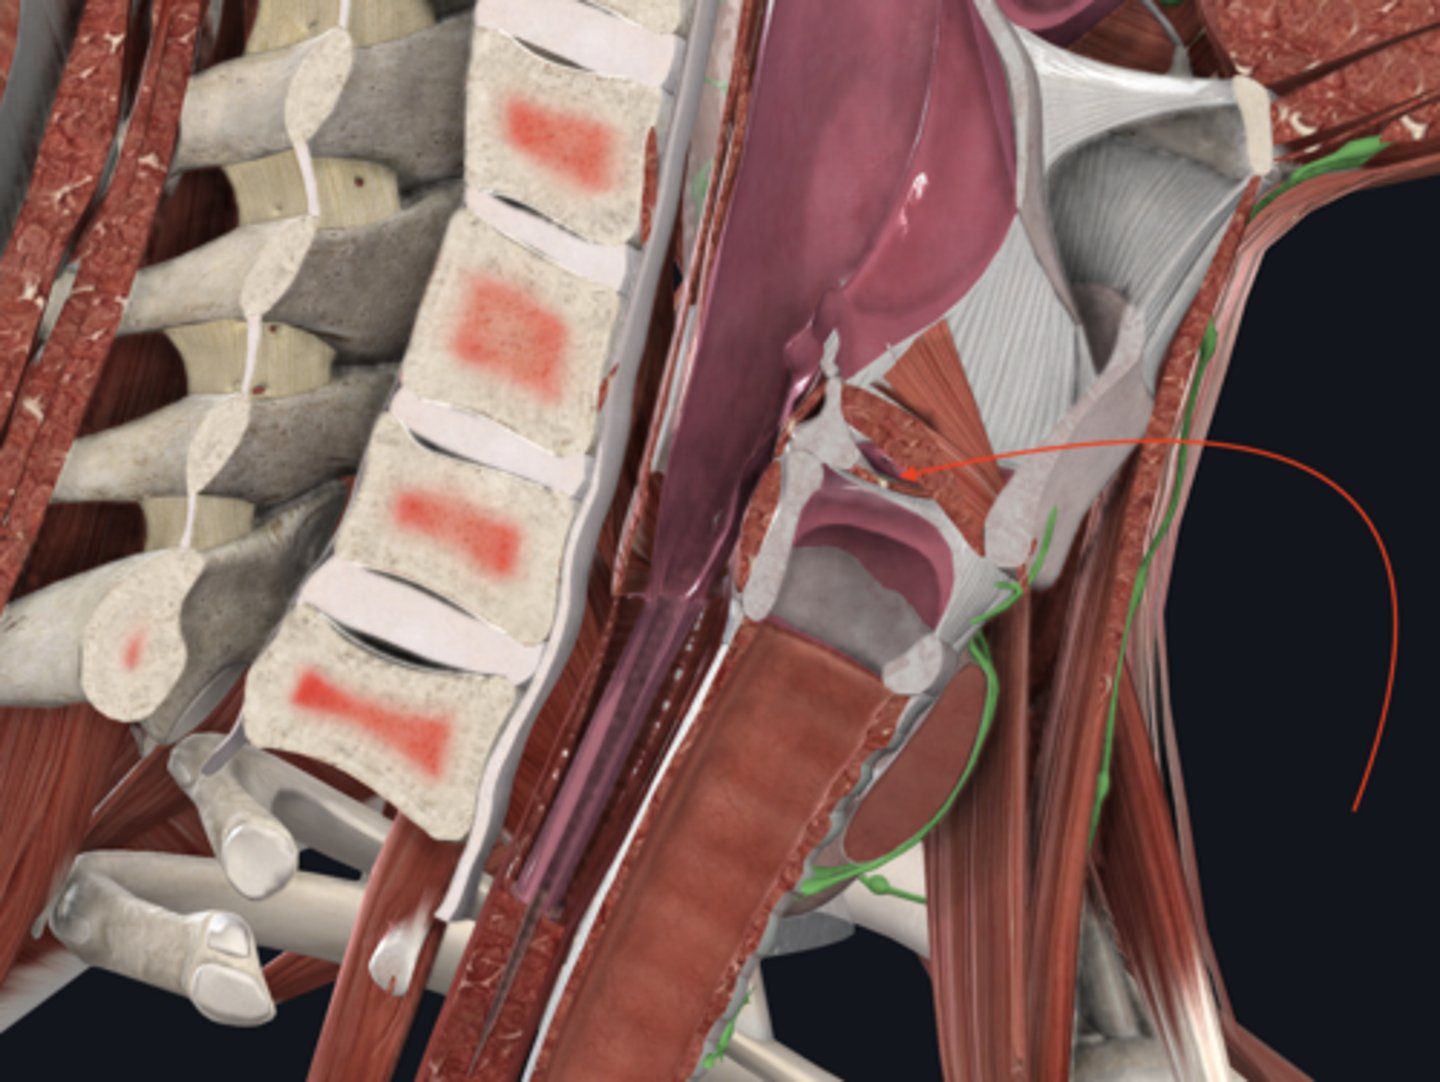

trachea

tracheal cartilages

annular ligament

right main bronchus

left main bronchus

lobar bronchi

terminal bronchi

diaphragm

anterior scalene

middle scalene

posterior scalene

sternocleidomastoid

intercostal muscles

pleural sac

serous membrane that surrounds the lungs and has a visceral and parietal layer